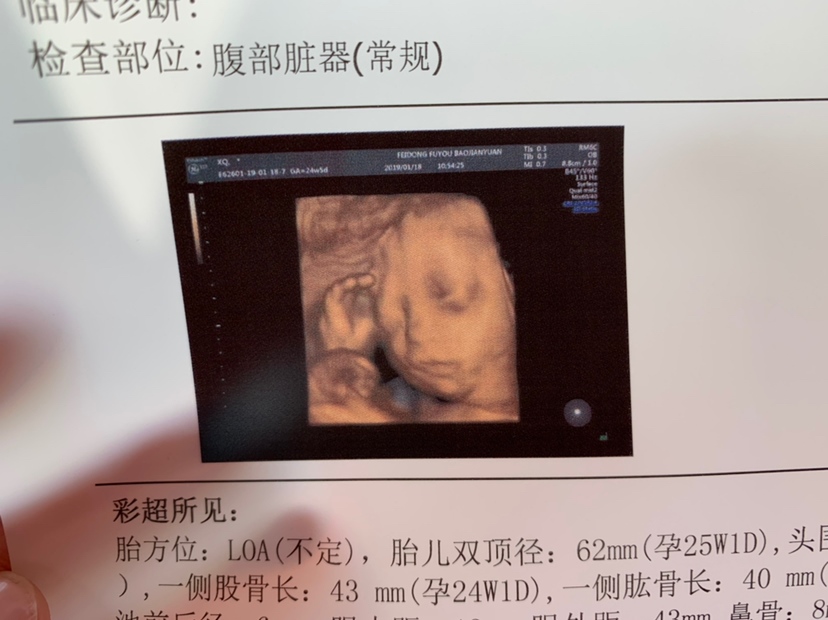

孕23周+2天

看不出来,但是挺可爱

你家孩子四维看着好清秀~

辛辛😘[帖主]:是的哦😊医生护士都这么说